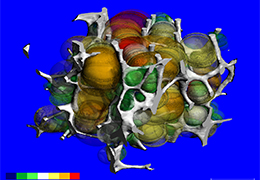

ANYTHINK 经导管主动脉瓣膜置换术分析系统